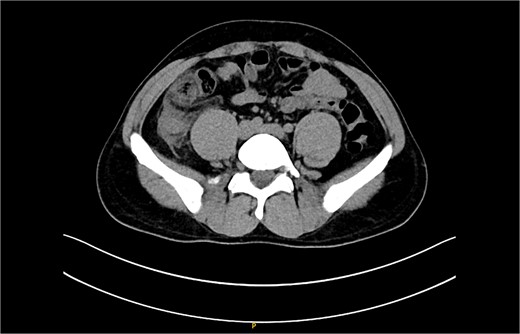

The non-contrast CT scan revealed a retrocecal appendix measuring 11 mm in diameter, with periappendiceal fluid and fat smudging, and reactive thickening of the cecum, indicating uncomplicated acute appendicitis. The patient was admitted to the surgical department and scheduled for a laparoscopic appendectomy (Figs 2 and 3).

CT scan picture with a coronal view showing acute inflamed appendix with peri-appendicular fat smudging, confirming the radiological finding of acute appendicitis.